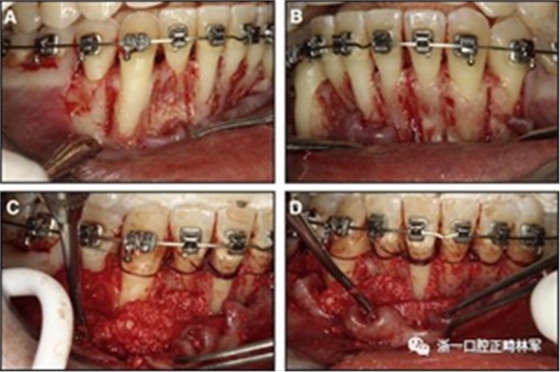

粘合保持器被移除,并放置固定裝置(圖15),僅限于患者要求的下頜弓。在第一階段牙周過(guò)程中,將結(jié)締組織移植物置于下頜右側(cè)中切牙的面?zhèn)取?個(gè)月后進(jìn)行第二階段牙周過(guò)程(圖16)。包括有意識(shí)的垂直骨質(zhì)評(píng)分以啟動(dòng)區(qū)域加速現(xiàn)象,以及顯著的面?zhèn)群蜕鄠?cè)植骨以糾正骨開(kāi)窗。

圖15.下頜右側(cè)中切牙區(qū)域軟組織移植前的初始排齊:A,正面視圖; B,咬合面視圖; C,軟組織移植2周后,初始牙周手術(shù)。

圖16.第二階段牙周手術(shù)階段,軟組織移植后2個(gè)月:A和B,這包括應(yīng)用骨形態(tài)發(fā)生蛋白,故意骨質(zhì)損傷引起局部加速現(xiàn)象,以及C和D,應(yīng)用植骨漿液糾正牙槽骨的開(kāi)窗(Colin Richman博士提供)。